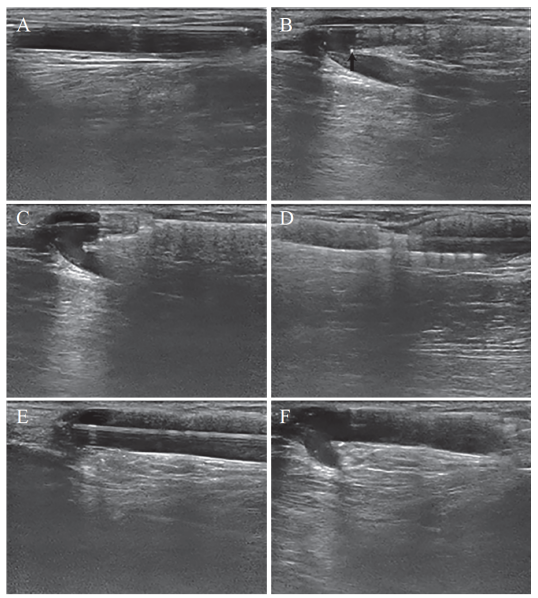

图2:超声引导下镍钛合金支架植入主要步骤的超声影像。A:支架植入前对狭窄的预扩张;B:支架释放前的定位,支架呈“鱼骨头”样回声,箭头所指为支架前端;C:支架前端锚定血管壁;D:支架释放完毕;E:对植入支架及狭窄的后扩张;F:扩张成形的支架。

结合本文及相关研究超声引导下支架释放有以下优势:(1)与X线血管造影相比,超声无辐射损害,减少医患的辐射暴露时间,减少了造影剂加重残余肾单位的损伤,同时超声检查价格低廉,可重复性高,符合卫生经济学要求。(2)超声行介入治疗可清晰地确定动静脉内瘘狭窄部位及长度,可有效地选择合适球囊及支架,且超声能够测量记录残留的血管内径,并能在支架植入后再次测量内径,同时能进行血流量测定,能有效评估手术。(3)在裸支架植入中,超声具有实时显像和细节观察等优势,上肢血管较为浅表,血管腔与血管壁及周围组织间、血管腔与介入器材间均有良好的超声显像对比,超声能很好地显示支架植入的细节。(4)支架释放过程中,头端锚定至关重要,尤其在支架开始释放但未锚定时,可能发生不同程度移位,需要实时地捕捉位移并及时调整,尽管DSA在路图下也可为支架释放提供位置参考,但实时性相对不足,释放过程本身可能带来组织移位,导致路图与实际位置有偏差。在超声引导下可以实时观察血管与支架的位置关系,结合合适的释放速度,可以保证最终释放位置的准确性。(5)对于贴近吻合口的病变,操作时需观察动脉、静脉、吻合口、狭窄和支架五者的相对位置,而AVF吻合口部位的血管立体构型相对复杂,超声多角度细节显像在该部位较DSA更具有优势。